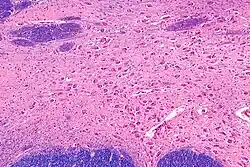

Neurons of the nucleus basalis are particularly vulnerable in age-related neurodegenerative diseases such as Alzheimer's disease,[3] Parkinson's disease, and several others.[2] The resulting decrease in acetylcholine in the brain is thought to contribute to the decline in mental function of affected patients.[3][2] For this reason, most currently available pharmacological treatments for dementia focus on compensating for faltering function of the nucleus basalis through artificially increasing acetylcholine levels. Because many other systems also are compromised in neurodegenerative diseases, the benefits of selectively increasing cholinergic function are limited.[12]

NBM in relation to the globus pallidus and putamen - very low magnification.

NBM - very high magnification.